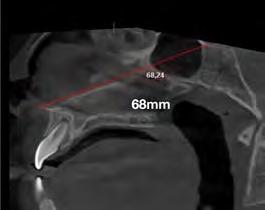

–MARPE, una alternativa a la disyunción en el paciente adulto, por el Dr. Enrique Solano y cols. [88]